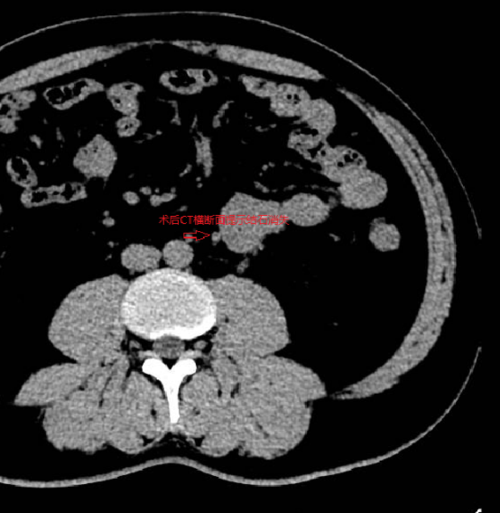

4月15日,在家难受了一天的王先生来到济南市中心医院东院区泌尿外科,CT检查提示“左侧输尿管结石并左肾积水”,结石大小约11×4.2×3.2mm。

CT检查锁定结石所在的位置

大小约11×4.2×3.2mm的结石是个什么概念?济南市中心医院东院区泌尿外科主任郭峰介绍说:“结石的大小相当于一粒花生米,这么大的结石难以自然排出体外,需要我们非常精准地进行碎石,并且需要确保碎石过程中避免对正常组织造成损伤,真正实现无创碎石。”